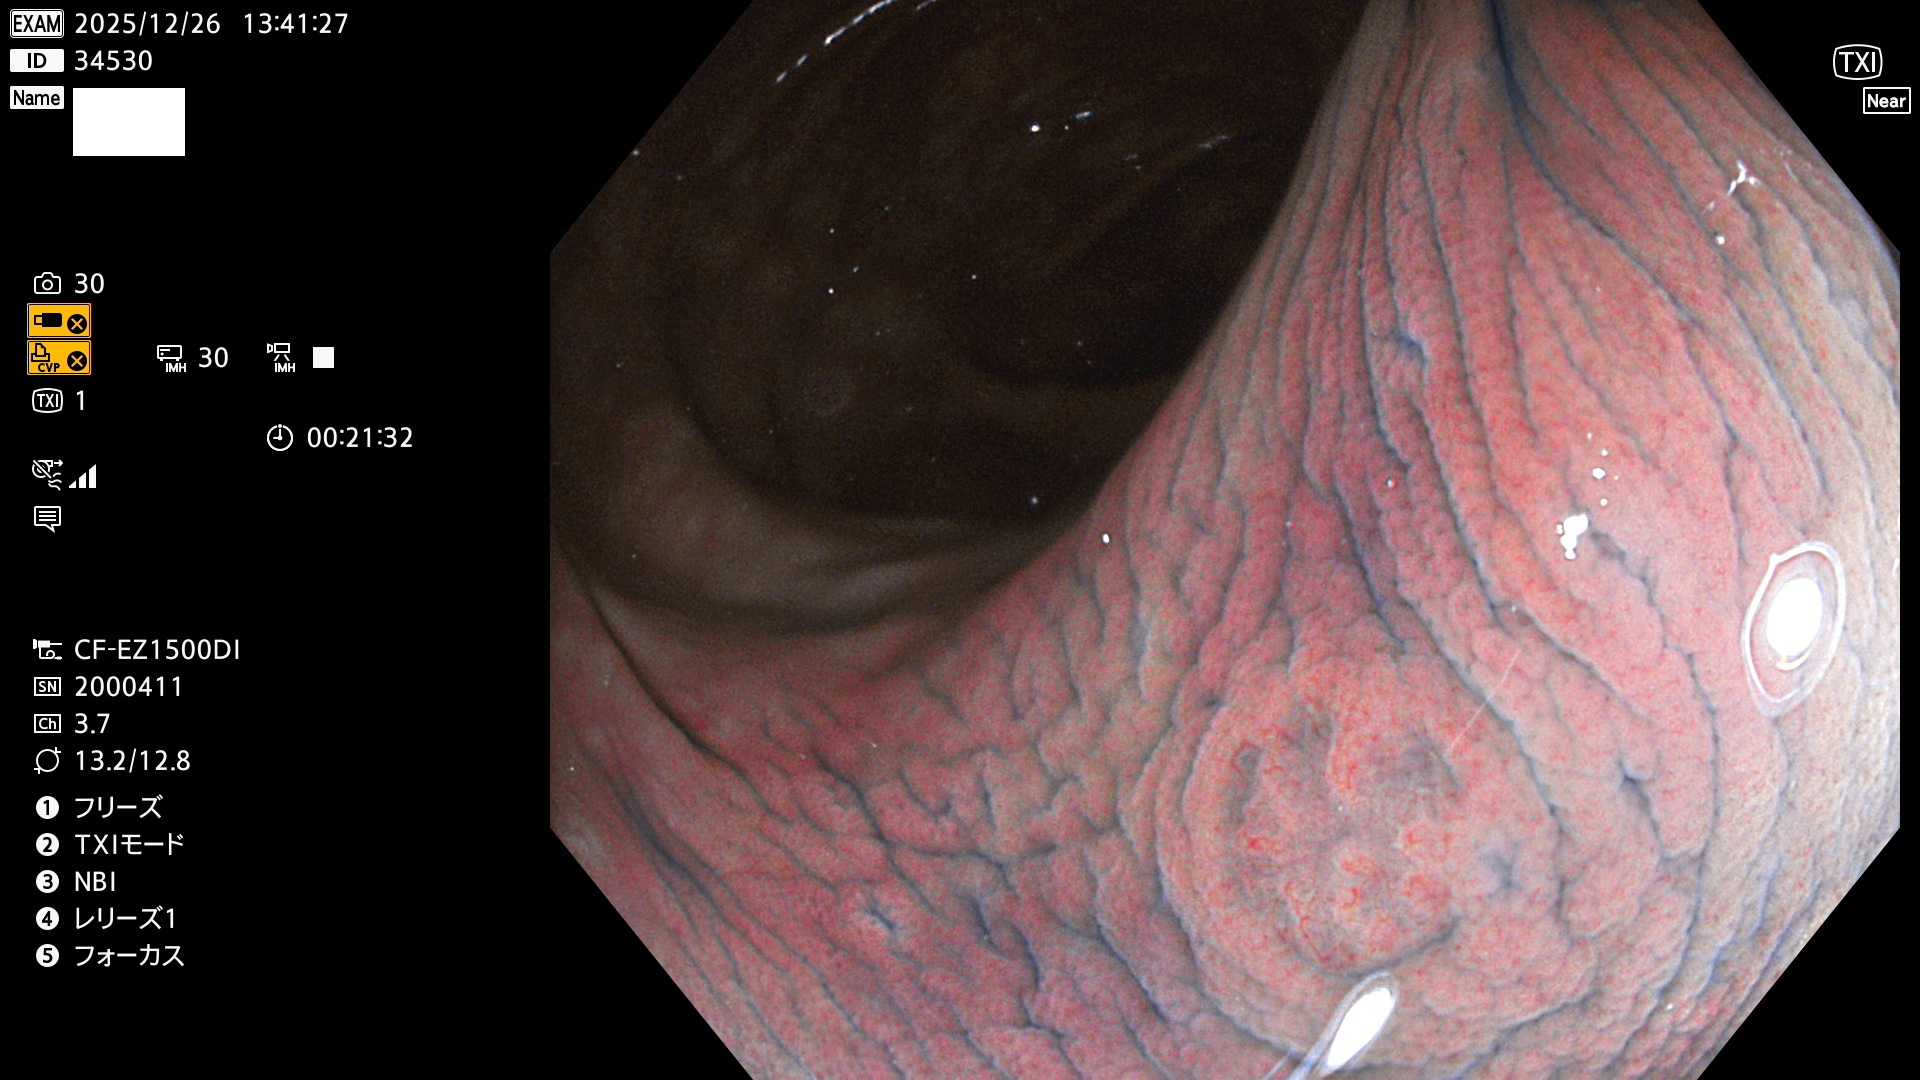

完全に平坦な物をUb、陥凹している物をUcと呼びます。Ubは認識が困難で、Ucはびらん(炎症)と紛らわしいために見落とされやすく、「内視鏡後・大腸癌」の原因になります。

毎週の検査(木・金・土・日)に発見されたUbとUc型・腺腫を、その週の日曜の夜にUPし1週間、提示します。

2025年12月18日〜12月29日の8日間(80件)13個 (Uc_ADR=13個/80人=16%)